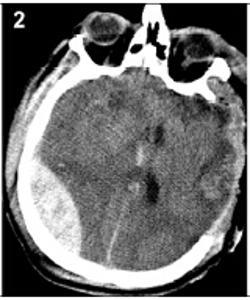

20160503094709

20160503094717

20160503094723

20160503094729